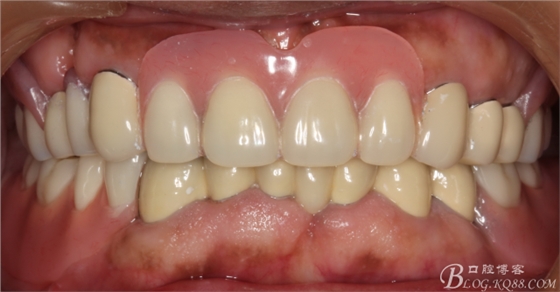

修復(fù)后效果圖,

說到咬合重建確是一個(gè)很復(fù)雜的命題,他需要醫(yī)生有很厚的修復(fù)功底,對(duì)待患者的咬合有一個(gè)正確的評(píng)價(jià),根據(jù)經(jīng)驗(yàn)對(duì)垂直患者的咬合距離得以正確的回復(fù)和重建。這個(gè)病例就是對(duì)原來的垂直距離抬高了2mm,修復(fù)后患者感覺非常舒服。